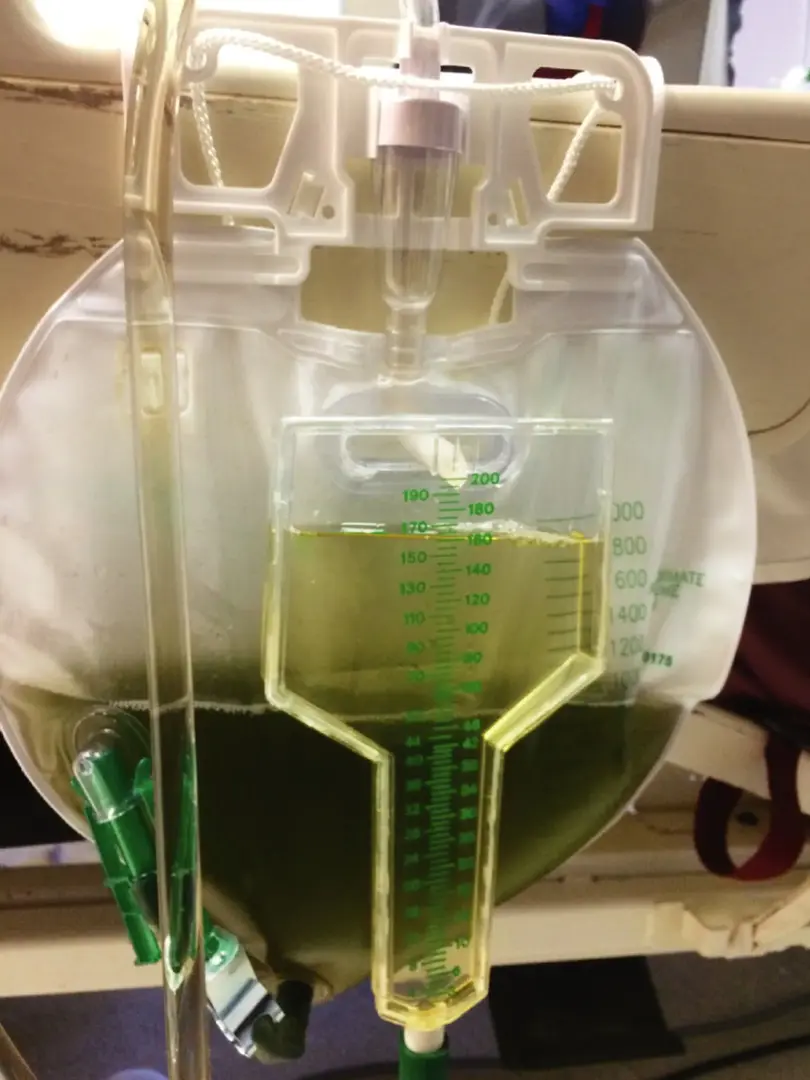

Hematúria pós infecção, caso clínicos para auxiliar no entendimento de causas glomerulares comuns e raras...